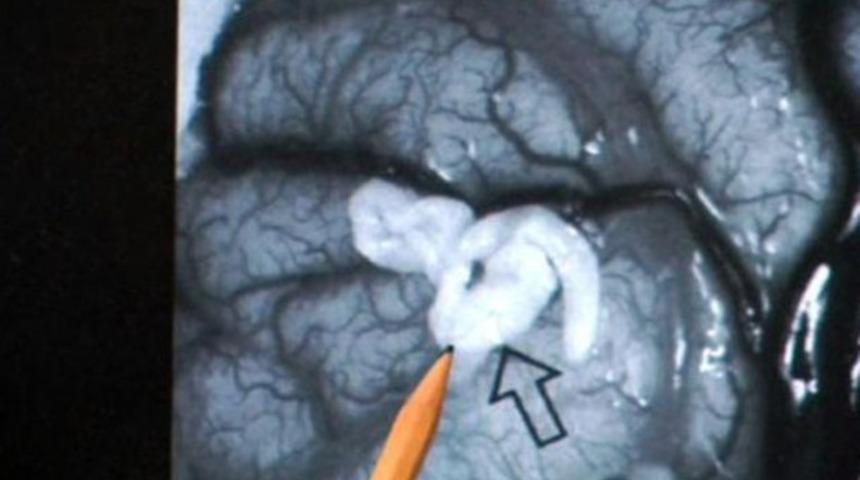

İngiltere'de 50 yaşındaki bir adamın beyninden 5 santimet uzunluğunda tenya çıkarıldı.

Chambridge Sanger Enstitüsü görevlisi bilim adamı Neuropatalog Andrew Dean, önce baş dönmesi ve kramp şikayeti ile hastaneye başvuran hastada tenyanın tesadüf olarak bulunduğunu söyledi. Focus dergisinin haberine göre, adamın beyninde dört yıl boyunca büyüyen 'Spirometra erinacei europaei' tipi tenyanın, İngiltere’de ilk kez ortaya çıktığı belirtildi. Ameliyat sonrası sıhhatine kavuşan ve adı açıklanmayan ingiliz'in Cambridge Üniversitesi Kliniği’nden taburcu olduğu belirtildi.